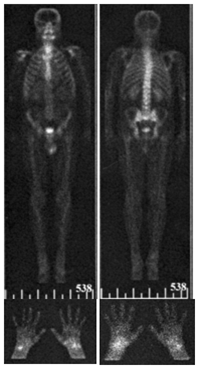

In December 2005 the patient felt himself well. He had no complains, gained 20kg in weight. All laboratory tests were normal as well as the abdominal CT. But in February 2006 articular pain resumed. Osteoscintigraphy with TC-99m pyrophosphate sodium was performed 03.03.2006 (Figure 1).

Figure 1 Ostheoscintigraphy with TC-99m labeled sodium pyrophosphate (03.03.2006).

There was increased accumulation of radiotracer in the projection of shoulder joints, wrist and ankle joints, small joints of hands and feet. In May 2006, the patient stopped taking antibiotics. For about one year he felt himself satisfactory. Gradually, however, the symptoms grew. In November 2007 the patient complained of unformed stool 1-2times a day, bloating, rumbling in abdomen; pain in wrist joints with swelling of periarticular tissue, pain in ankle joints, small joints of the hands and feet without swelling, pain in the cervical and lumbar spine.